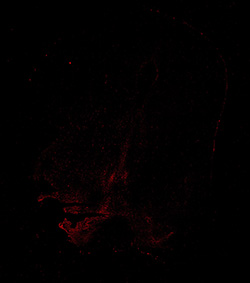

An anatomical analysis of the developing human midbrain from 6 post-conceptional weeks (PCW) to 22 PCW reveals increased tissue complexity, characterized by the emergence of dopaminergic nuclei, as highlighted by immunofluorescence analysis for tyrosine hydroxylase (TH).

TH

11PCW human midbrain